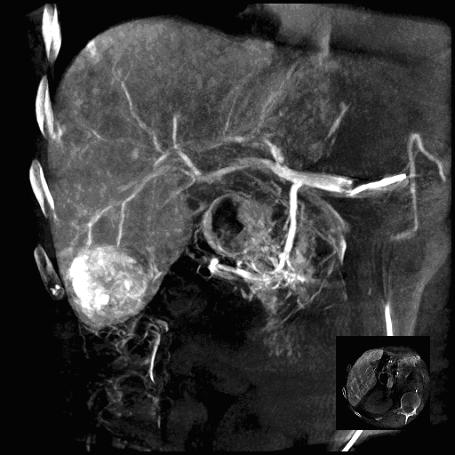

Врачи отмечают, что ангиография печени является важным инструментом для диагностики и оценки сосудистых заболеваний этого органа. Методика позволяет визуализировать кровеносные сосуды, что помогает выявить опухоли, аневризмы и другие патологии. Специалисты подчеркивают, что правильная подготовка пациента и использование современных технологий, таких как компьютерная томография с контрастированием, значительно повышают точность исследования. Кроме того, врачи акцентируют внимание на необходимости соблюдения мер безопасности, чтобы минимизировать риски, связанные с введением контрастного вещества. В целом, ангиография печени считается высокоинформативным методом, который способствует более точной постановке диагноза и выбору оптимального лечения.

Визуализация процессов гемодинамики, или кровотока в печени обычно относится к селективным методам обследования и реализуется как целиакография – серия снимков чревного ствола, отходящего от брюшной аорты.

Если «точкой входа» препаратов является общая печеночная артерия, говорят о гепатикографии. Также могут быть использованы методики заполнения контрастом ветвей воротной вены (портография).

Потребность в ангиографии печени возникает, если есть необходимость оценить состояние сосудистого русла органа. Также с помощью исследования можно выявить новообразования, которые имеют особенности кровоснабжения, но нередко плохо видны или вовсе не выделяются на рентгеновских снимках или экране аппарата УЗИ без контраста.